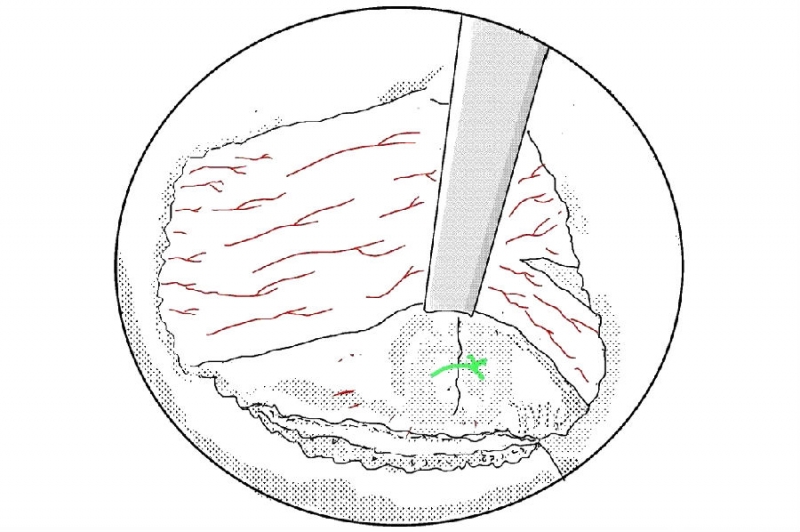

5. 使用小的射频刀头在止点区域进行止血;

10. 剥离黄韧带;

11. 用UBE拉钩牵开神经根;

12. 突出间盘表面的预止血和神经根周围束带的切除;

13. 使用髓核钳摘除突出的髓核组织;

14. 你可以选择使用等离子电凝皱缩来缩小裂口;

15. 或者是纤维环缝合修复;